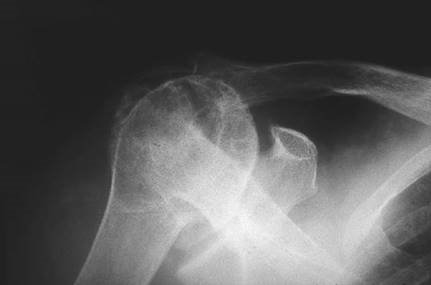

Describe the radiograph. What is your diagnosis?

T his is an AP view of the right shoulder showing a deformed humeral head with loss of joint space and subchondral sclerosis. This is osteoarthritis with a degree of avascular necrosis.

This is a 70-year-old fi t and healthy patient with signifi cant pain and stiff ness. She has failed a trial of non-operative treatment. She wants surgery. What will you off er her? Explain how you would consent her.

I would off er her a shoulder hemiarthroplasty. I would explain to her that the procedure would not restore full movement in her shoulder, although the range of movement is likely to improve. The procedure is very good for pain relief. The procedure would be carried out under GA or regional anaesthesia. She is likely to stay in hospital for 2โ€“3 days and will have to wear a sling for approximately 3 weeks and avoid external rotation to protect a repaired tendon (subscapularis). Her mobilization would be monitored by physiotherapists. The risks of the procedure include infection, injury to nerves and blood vessels, incomplete relief of symptoms, and implant loosening.

What surgical approaches are you aware of?

T he procedure can be carried out through a Mackenzie (antero-superior) approach or a deltopectoral approach.

If the patient had a massive cuff tear, what would you do?

I f the patient were to have a massive cuff tear, the outcome following hemiarthroplasty has been reported in the literature to be less satisfactory. This patient is unlikely to get any signifi cant relief from non-operative treatments.

Counselling is needed before proceeding to hemiarthoplasty.